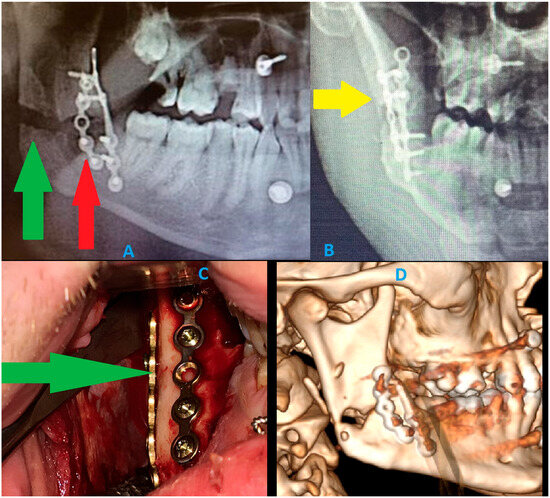

When CBCT Looks Borderline and Standard Radiology Is Inconclusive: Should We Plate or Should We Wait?

by Ömer Uranbey, Ece Gülbağ, Büşra Ekinci, Angela Rosa Caso, Jan Nienartowicz, Krzysztof Żak and Kamil Nelke

Diagnostics 2025, 15(24), 3140; https://doi.org/10.3390/diagnostics15243140 - 10 Dec 2025

The main role of panoramic radiography lies in its rapid screening capability and its ability to detect and identify bone lesions, pathologies, and tooth-bearing structures. Since panoramic radiographs are widely used, they provide a good view of the jaw bones, maxillary sinus, and [...] Read more.

The main role of panoramic radiography lies in its rapid screening capability and its ability to detect and identify bone lesions, pathologies, and tooth-bearing structures. Since panoramic radiographs are widely used, they provide a good view of the jaw bones, maxillary sinus, and temporomandibular area. However, their major limitation is the reduced ability to accurately assess bone conditions, particularly in evaluating cortical integrity or identifying subtle, nondisplaced, or greenstick-type fracture lines. Other limitations include the presence of artifacts, image distortion, magnification variability, and high sensitivity to patient and film positioning, all of which can compromise image quality and diagnostic confidence. This 2D imaging method is still used worldwide, especially by dentists; however, this type of radiograph can be unpredictable due to structural superimposition and reduced ability to clearly establish, measure, and verify the precise dimensions, boundaries, and areas occupied by selected lesions. Many patients undergo panoramic imaging to assess possible mandibular fractures after trauma or following the removal of cysts, tumors, or impacted teeth. In most cases, the occurrence of a fracture without displacement can be misjudged, omitted, or underestimated. In such cases, either cone-beam computed tomography is performed or a detailed clinical examination before or during surgery, followed by intraoperative assessment, helps identify a possible fracture line, bone bending, mandibular instability, or the potential need for simultaneous prophylactic plating during dental procedures or the use of maxillomandibular fixation. This paper presents the author’s own experience regarding the limitations of panoramic radiographs in estimating bone condition and detecting fracture lines. Therefore, it is essential to highlight the role of prophylactic (preventive) mandibular plating (PMP) or fixation and to clarify when it should be considered. Full article

Figure 1